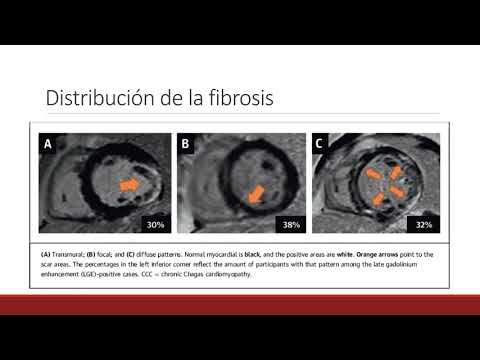

Cicatriz ventricular izquierda y pronóstico de la miocardiopatía chagásica crónica. Dra. María Eugenia Doppler. Residencia de Cardiología. Hospital C. Argerich. Buenos Aires